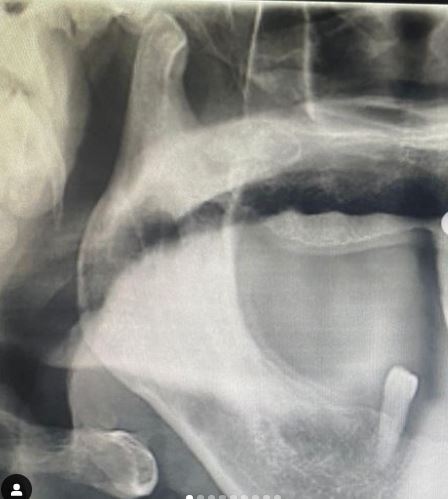

Cerrahi Çene Eklemi Tedavisi

Çene Eklemi Cerrahisi

Çene Eklemleri Tedavisi